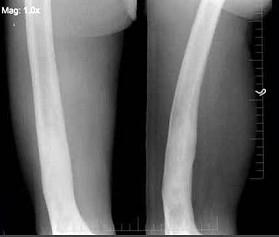

问题 58岁男性,因右大腿酸痛,弯曲变形,既往有外伤史,右股骨摄片如图所示,下列诊断最为合适的是 ( )

选项 A、慢性硬化性骨髓炎 B、以上都不是 C、慢性骨髓炎 D、骨质软化症 E、硬化性骨纤

答案 C